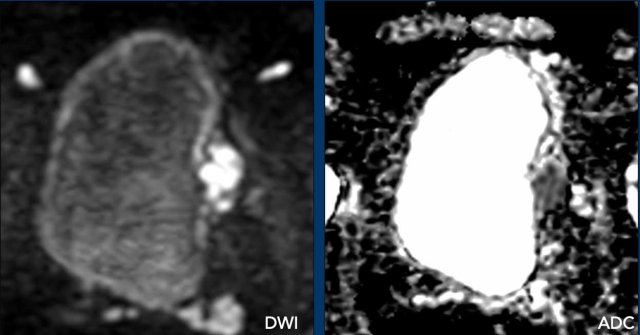

• Diffusion: restricted diffusion with high SI on DWI and low SI on ADC.

Final VI-RADS score: 1

You can appreciate the high signal intensity of the tumor on DWI and low intensity in ADC sequence.

The tumor stalk has low intensity on DWI and high intensity on ADC.

Score

• T2W: 2

• DCE: 2

• DWI/ADC: 2

Final VI-RADS score: 2